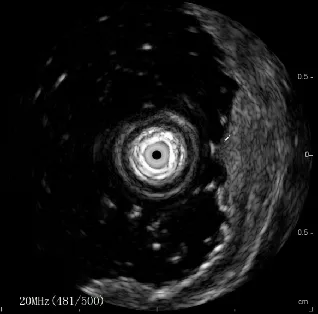

超声胃镜病灶处胃壁增厚,呈等回声改变,最厚约4.2mm,病变局限于黏膜层,黏膜下层连续、完整